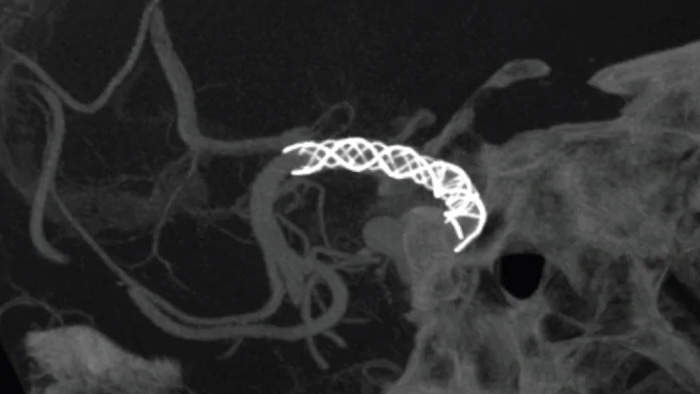

Vea claramente los perforadores cerebrales y los dispositivos difíciles

SmartCT Vaso IA

Mejore la visualización de stents endovasculares, diversores de flujo y otros dispositivos, así como la morfología vascular hasta el nivel del perforador con SmartCT Vaso. Esta técnica de adquisición se basa en una exploración por TAC de haz cónico y una inyección de contraste intraarterial. Se utiliza cada vez más para el seguimiento de aneurismas tratados con stents diversores de flujo para comprobar la ubicación del dispositivo.